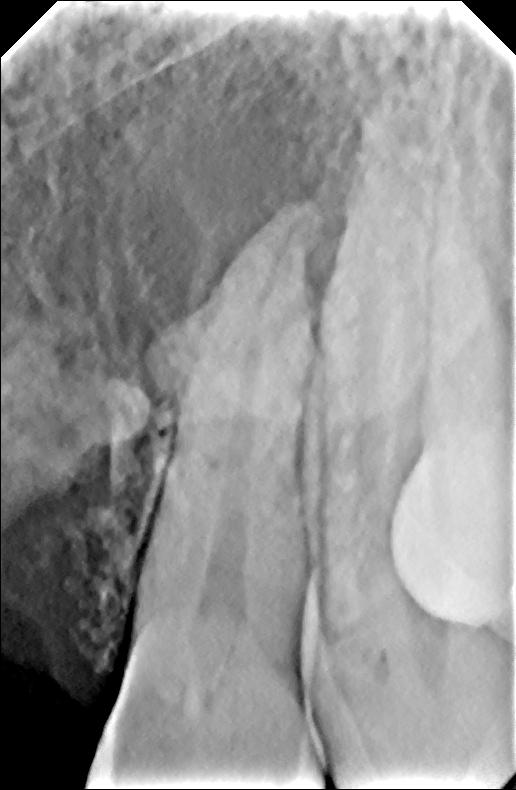

Готовлюсь к имплантации. Сделали снимки: киста на 22, 23 зубах. Назначили лечение, затем через два месяца цистэктомия. Очень опасаюсь, что до этого момента случиться обострение, вплоть до удаления зуба.

И каковы шансы на успешную имплантацию по снимку? Лечение назначено через неделю.

По этому снимку невозможно планировать операцию и диагностировать Вашу проблему. Успех операции на 36 зубе зависит от профессионализма хирурга, условия хорошие. Что касается передних зубов — к сожалению, по этому снимку ничего не видно. Приезжайте ко мне, я Вас посмотрю.